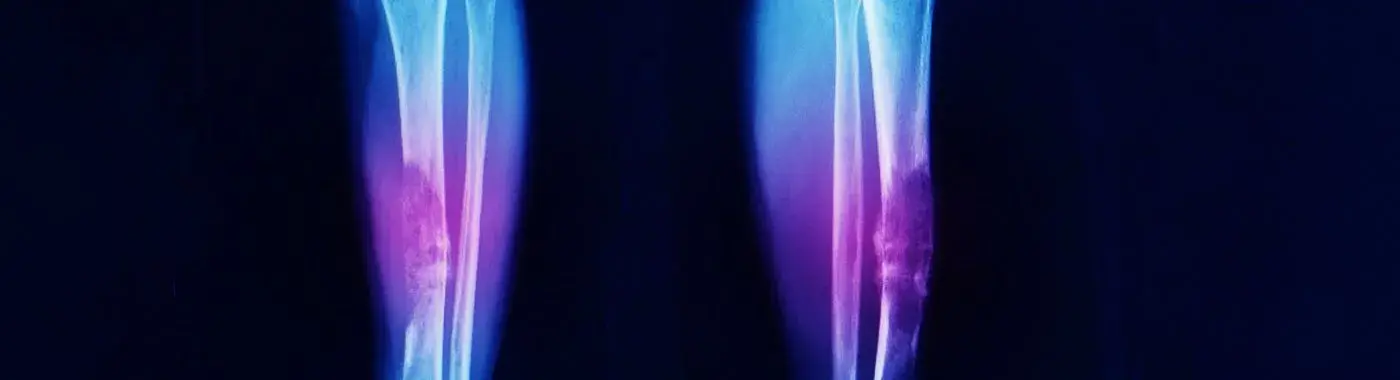

Chondroblastoma is a benign tumor that originates from chondroblasts, the cells responsible for cartilage formation. It most commonly occurs in the long bones, particularly around the knee, but can also be found in other areas such as the pelvis and spine. Chondroblastomas are most frequently diagnosed in adolescents and young adults, typically between the ages of 10 and 25. Although these tumors are non-cancerous, they can cause pain, swelling, and limited mobility, necessitating medical intervention.

• Imaging Studies: X-rays are typically the first imaging modality used. They can reveal characteristic features of chondroblastoma, such as a lytic bone lesion. MRI or CT scans may be used for further evaluation.